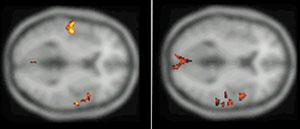

Именно наличие клиники во многом определяет возможности фундаментальных и прикладных исследований ИМЧ. Поэтому прежде всего несколько слов о ней. У нас прекрасные высококвалифицированные доктора и медсестры. Без этого нельзя: ведь мы на переднем крае, и нужна высочайшая квалификация, чтобы выполнять нерутинное, новое. У нас выполняются практически все стандартные манипуляции и наряду с ними и хирургическое лечение эпилепсии и паркинсонизма, проводятся психохирургические операции, в том числе и хирургическое лечение обусловленного героином обсессивно-компульсивного синдрома, знаменитая «пересадка мозга», точнее имплантация фетальной мозговой ткани, лечение магнитости-муляцией мозга, лечение афазии с помощью электростимуляции и многое другое. Накоплен десятилетний опыт клинических обследований с помощью позитронно-эмиссионной томографии. На рисунках приведена малая толика того, что может диагносцировать этот метод томографии. У нас лежат тяжелые больные, и мы стараемся помочь с помощью вышеперечисленных методов даже тогда, когда все остальные попытки были неудачны. Конечно, это удается не всегда. Но безграничных гарантий в лечении людей дать невозможно, а если кто-то дает их, это всегда вызывает очень серьезные сомнения.

Вообще, благодаря технике позитронно-эмиссионнной томографии (или сокращенно ПЭТ), стало возможно детальное изучение одновремено всех областей мозга, отвечающих за сложные “человеческие” функции мозга. Суть метода состоит в том, что малое количество изотопа вводят в вещество, участвующее в химических превращениях внутри клеток мозга, а затем наблюдают, как меняется распределение этого вещества в интересующей нас области мозга. Если к этой области усиливается приток глюкозы с радиоактивной меткой - значит, увеличился обмен веществ, что говорит об усиленной работе нервных клеток на этом участке мозга.

А теперь представьте, что человек выполняет какое-то сложное задание, требующее от него знания правил орфографии или логического мышления. При этом у него наиболее активно работают нервные клетки в области мозга, “ответственной” именно за эти навыки. Усиление работы нервных клеток можно зарегистрировать с помощью ПЭТ косвенно, по увеличению локального кровотока в активированной зоне. (Более ста лет назад было показано, что усиленная работа нервных клеток приводит к увеличению локального мозгового кровотока в этой области.)

Таким образом, удалось определить, какие области мозга “отвечают” за синтаксис, орфографию, смысл речи и за решение других задач. Мы предъявляем испытуемым различным образом организованные задания, при выполнении которых необходимо «задействовать» определенные свойства речи. Например, отдельные слова, предложения, связный текст. Сравнивая ПЭТ изображения, получаемые при этой деятельности, мы можем определить, где в мозге происходит обработка отдельного слова, где синтаксиса, а где смысла текста. Видны зоны, активирующиеся при предъявлении слов, неважно, надо ли было их читать или нет. Зоны, отвечающие за смысл текста, и другие. Интересно, и это будет рассмотрено ниже, что удалось обнаружить зоны, активирующиеся, чтобы «ничего не делать».

В исследованиях мозговых механизмов восприятия речи по результатам ПЭТ исследования с использованием локального кровотока обнаружено, что при чтении текста основные изменения происходят в области левой височной доли (38, 22, 43, 41, 42, 40 и 38 поля), 3, 4, 6, 44, 45, и 46 полей и справа в области 22, 41, 42, 38, 1, 3, и 6 полей. Сопоставление с данными других исследователей позволяет соотносить некоторые из этих результатов с процессами запоминания, чтения слов, понимания смысла. Появилась возможность выделить области, связанные с восприятием смысла и запоминанием текста, от областей, которые связаны с обработкой отдельных слов. Эти результаты коррелируют с полученными ранее с помощью анализа нейронной активности. Были также подтверждены результаты, полученные при исследовании нейронной активности, о вовлечении в обеспечение речи, наряду с классическими зонами, участков мозга, расположенных в других областях. При исследовании мозгового обеспечения речи картированы области коры мозга человека, участвующие в обеспечении различных стадий анализа орфографиче-ских и синтаксических характеристик. Показано, что медиальная экстрастриарная кора вовлечена в обработку орфографической струк-туры слов; значительная часть левой верхневисочной коры (зона Вернике) наиболее вероятно участвует в произвольном семантическом анализе, и менее вероятно - обработке синтаксической структуры; нижняя лобная кора левого полушария является звеном системы вербального семантического анализа, ее возможное участие в синтаксической обработке ограничено обработкой словоформ и функциональных слов, но не порядка их следования в предложении; в определение синтаксической структуры фразы на основе анализа порядка следования слов вовлечена передняя часть верхневисочной коры. На основе анализа мозгового кровотока удалось показать, что, когда человеку предъявляется связный текст даже без необходимости его читать,- задание было считать появления определенной буквы - мозг тем не менее существенно, более интенсивно вовлекается в обработку лингвистических характеристик стимулов, что выражается в активации определенных зон, чем при предъявлении с тем же заданием тех же слов, но несвязанных, перемешанных в случайном порядке.

Мозговая система непроизвольной синтаксической обработки. Проекции на латеральные поверхности полушарий мозга областей активации (p < 0,01), полученных в условиях поиска буквы в связном тексте, предъявляемого бегущей строкой, в сравнении с аналогичной задачей при предъявлении синтаксически |

Активация мозга в условиях обработки текста. Области локального повышения функциональной активности нервной ткани, полученные в условиях задачи на понимание читаемого текста, по сравнению с задачей поиска буквы в бессмысленной буквенной последовательности. Показаны проекции зон значимых (p < 0,0001) активаций на три ортогональных плоскости (вид справа, сзади и сверху, соответственно, в верхнем ряду справа и слева, в нижнем ряду - слева). Внизу справа показаны проекции кортикальных латеральных активций в левом полушарии на реконструированную поверхность левого полушария «стандартного» мозга. |